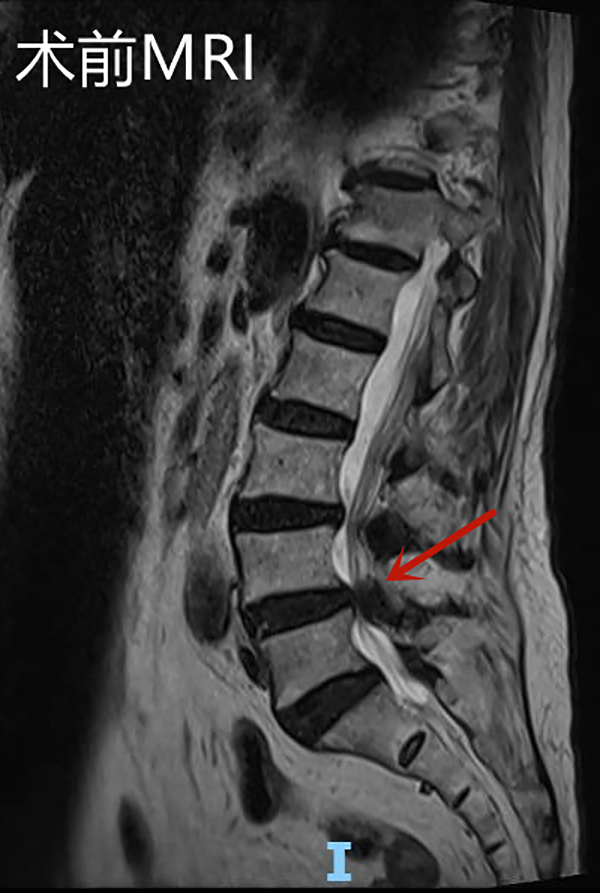

邱奶奶入院后查腰椎磁共振顯示L4/5椎管嚴重狹窄,神經根受壓,明確診斷為腰椎管狹窄癥。腰椎骨狹窄癥是老年人群常見的腰椎退行性疾病。狹窄可以發生在中央椎管、側隱窩以及椎間孔等部位,由于椎管或神經根管的狹窄,致使椎管內神經受壓,神經功能障礙,可表現為腰痛、下肢疼痛或麻木,隨著病情的發展可出現下肢運動及感覺障礙。

手術后復查腰椎MRI顯示:相應的椎管狹窄及神經根壓迫已解除,手術后第2天邱奶奶便可下地行走,腰痛及左下肢疼痛緩解,復查腰椎磁共振見L4/5左側狹窄已完全解除。手術后第4天,患者順利出院,沒有出現任何手術并發癥。